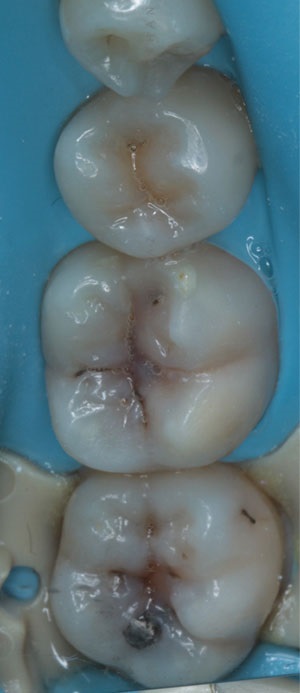

In this case, 27um aluminium oxide particles were used at a pressure of no more than 4-bar for 20 seconds. The cavity preparations are shown in Fig. 3.

• Figure 3